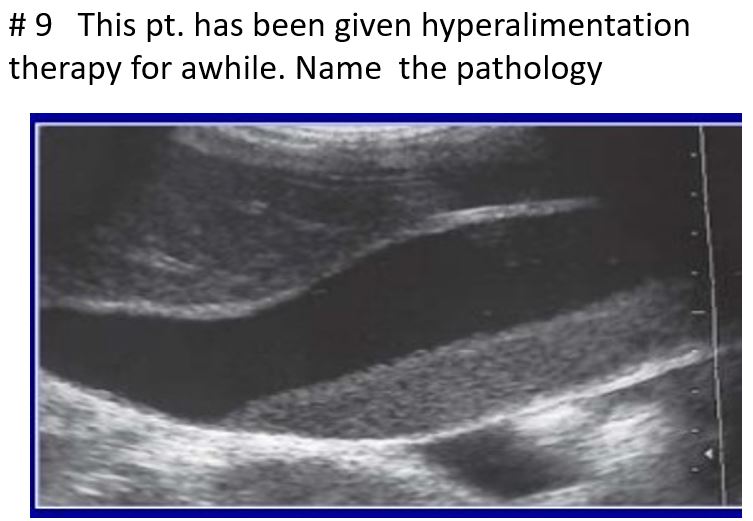

prolonged fasting, hyperalimentation therapy, or with obstruction of the gallbladder.

May be asymptomatic

Gravity dependent

Prominent GB size

slowly resettle as the patient changes their position

abnormal finding because either a functional or a pathologic abnormality exists when calcium bilirubin or cholesterol precipitates in bile

will not present with gallbladder wall thickening or internal vascularity

may also be seen in combination with cholelithiasis, cholecystitis, and other biliary diseases.

Sludge

sludge